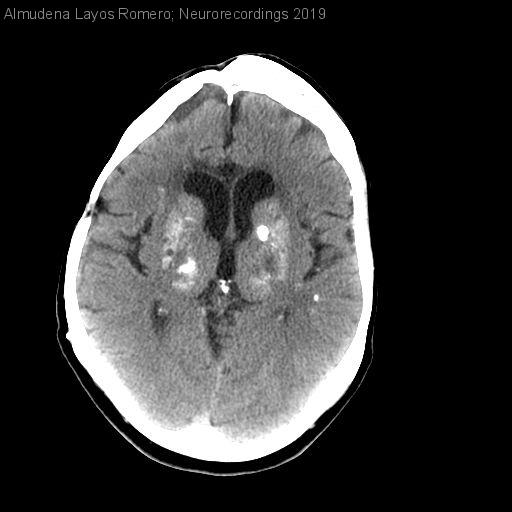

Hombre | 43 años

Diagnóstico final: Discinesias paroxísticas no cinesogénicas sintomáticas

Varón de 43 años con antecedentes de craneofaringioma intervenido en 1985 y tratamiento adyuvante con cobaltoterapia. Poco después desarrolló una disartria, hemiparesia izquierda y distonía generalizada con movimientos coreiformes con la distracción. Recientemente tiene episodios de...